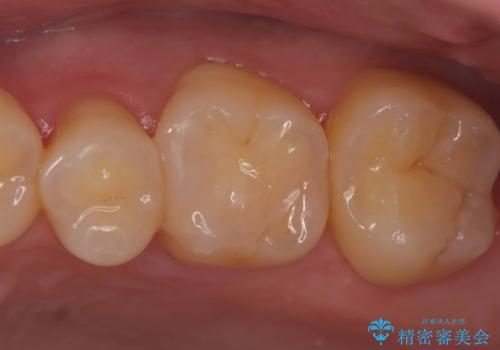

- 当院にて根管治療を行いましたが、病変の改善が得られなかったため、インプラント治療を行う方針といたしました。

抜歯即時埋入の適応と判断し、抜歯当日にインプラント埋入を行う「抜歯即時埋入」にて処置を実施しました。